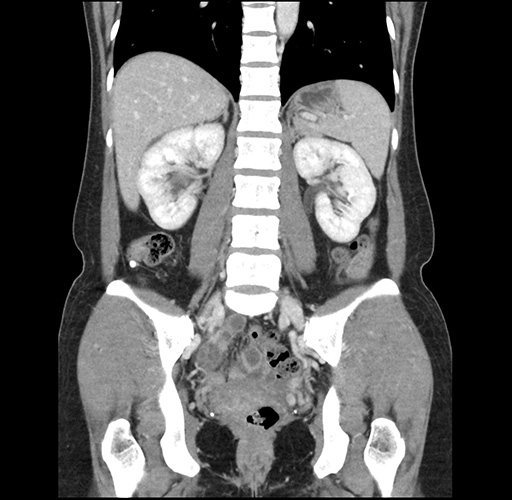

Imaging Analysis

Look through the patient's CT scan to identify any areas of concern for the necessary procedure.

Based on your CT findings, which issue(s) would give reason for "planned slowing down moment(s)" in this case?